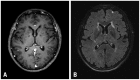

Purpose: Single dose gadolinium (Gd) enhanced fluid-attenuated inversion recovery (FLAIR) is helpful for visualizing superficial parenchymal metastases. However, the usefulness of FLAIR with a higher dose of Gd is uncertain. The aim of our study was two-folds: first, to prove that the signal to noise ratio (SNR) of small brain metastases is higher than large brain metastases on double-dose (DD) enhanced FLAIR and, second, to explore the added value of DD Gd enhanced FLAIR in relation to T1 GRE for evaluating small brain metastases.

Results: The SNR and CR of small brain metastases were significantly higher than those of large brain metastases (p<0.001). In qualitative analysis, the diagnostic sensitivities for small brain metastases were significantly higher for 3D T1 GRE plus 3D T2 FLAIR than 3D T1 GRE alone regardless of scan time (p<0.001).

Conclusion: Small brain metastases showed higher signal intensity than large brain metastases on the DD Gd enhanced 3D T2 FLAIR images. DD Gd enhanced 3D T2 FLAIR imaging may have a complementary role to 3D T1 GRE for evaluating small brain metastases.